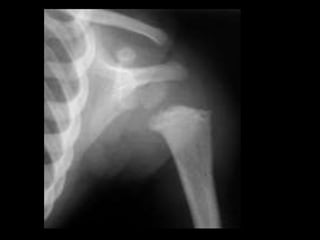

Fraturas de

costelas

Fraturas bilaterais

múltiplas.

Note os calos

posteriores e laterais

nas costelas e na

clavícula esquerda.

Calos com diferentes graus, sugerindo

fraturas de idades diferentes.

Murray, 2008

Fraturas de costelas Fraturas bilaterais múltiplas. Noteos calos posteriores e laterais nas costelas e na clavícula esquerda.

Calos com diferentesgraus, sugerindo fraturas de idades diferentes. Murray, 2008